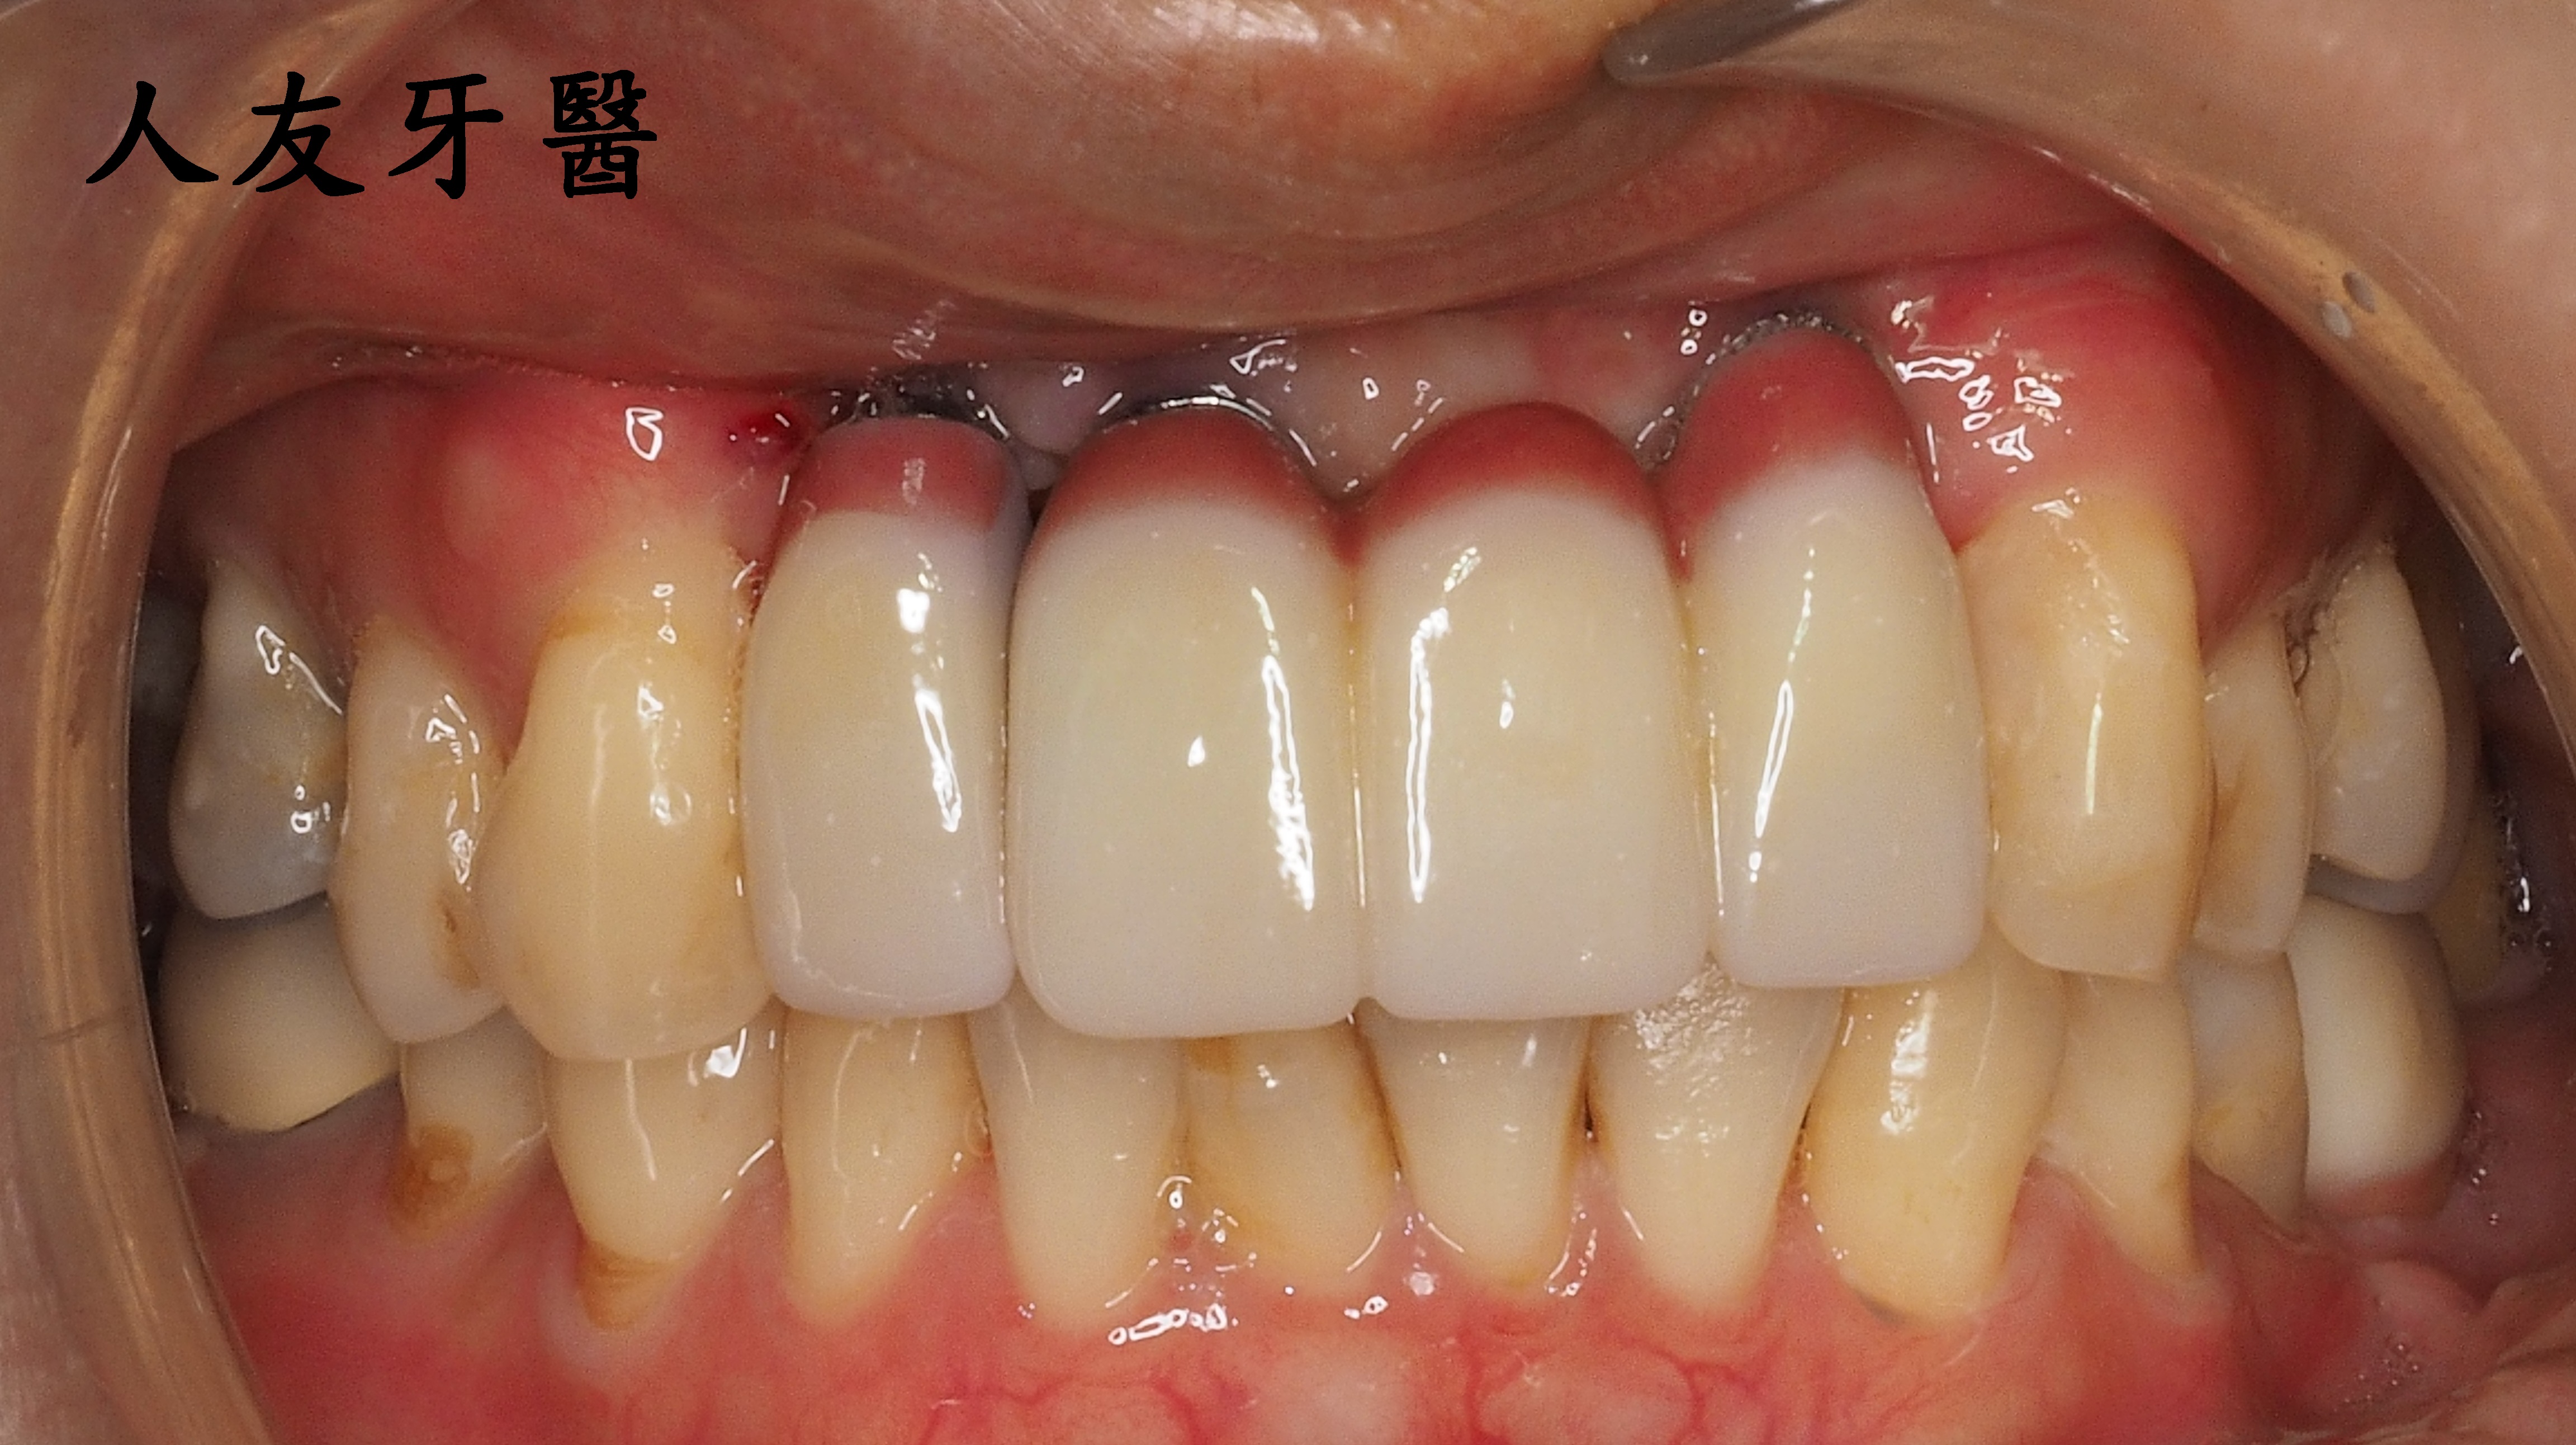

植牙完成後有幫牙套做牙肉色,牙齒才不會看起來太長。患者也不再抗拒看牙齒,說話口齒也很清晰。門面美觀又自然。